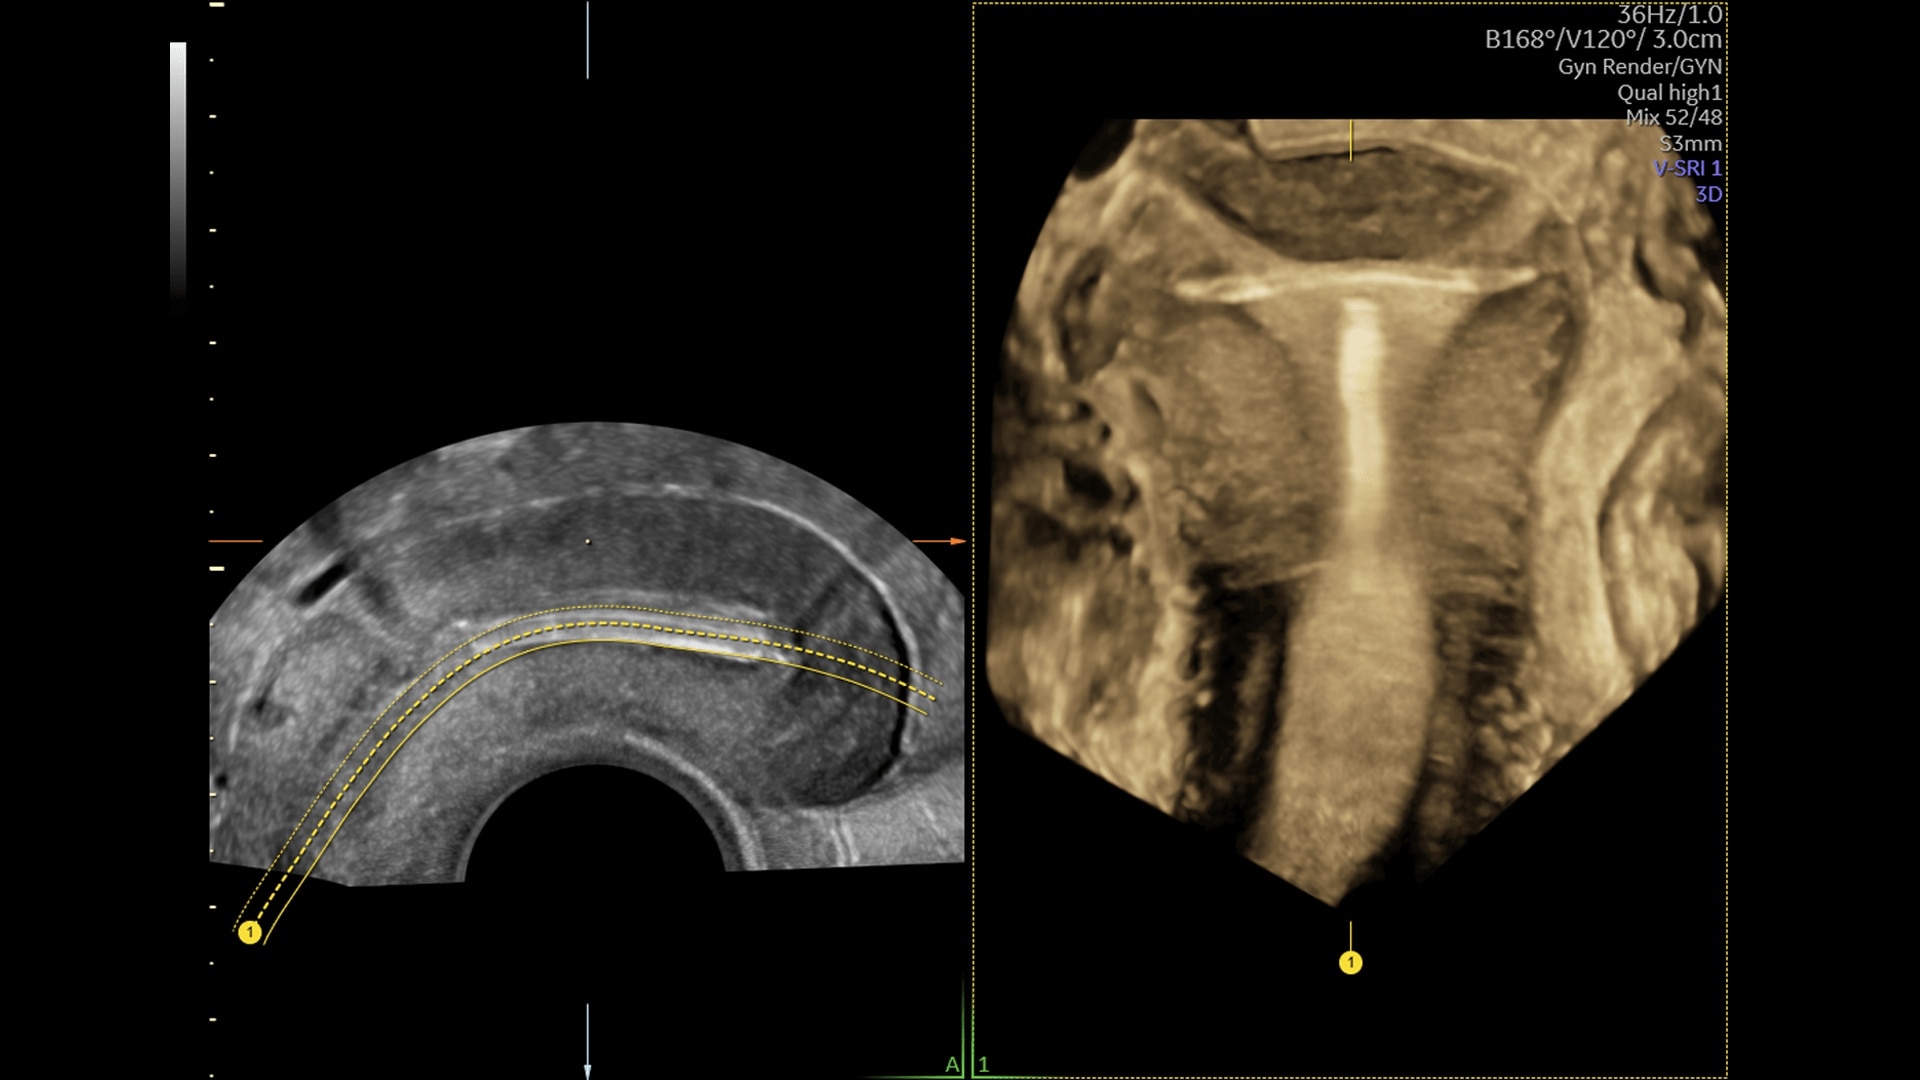

Unique Probe Technology

Obtain high resolution images with advanced probe technology - eM6C, RIC6-12, and RM7C